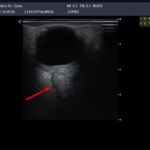

Imágenes E y F: ecografía ocular derecha: a nivel retroorbitario en el ojo derecho y en el área correspondiente a la inserción del nervio óptico, se observa una imagen asimétrica con relación al contralateral de ecoestructura sólida ubicada en la vaina del nervio óptico las medidas 11,7 x 9,8 mm.